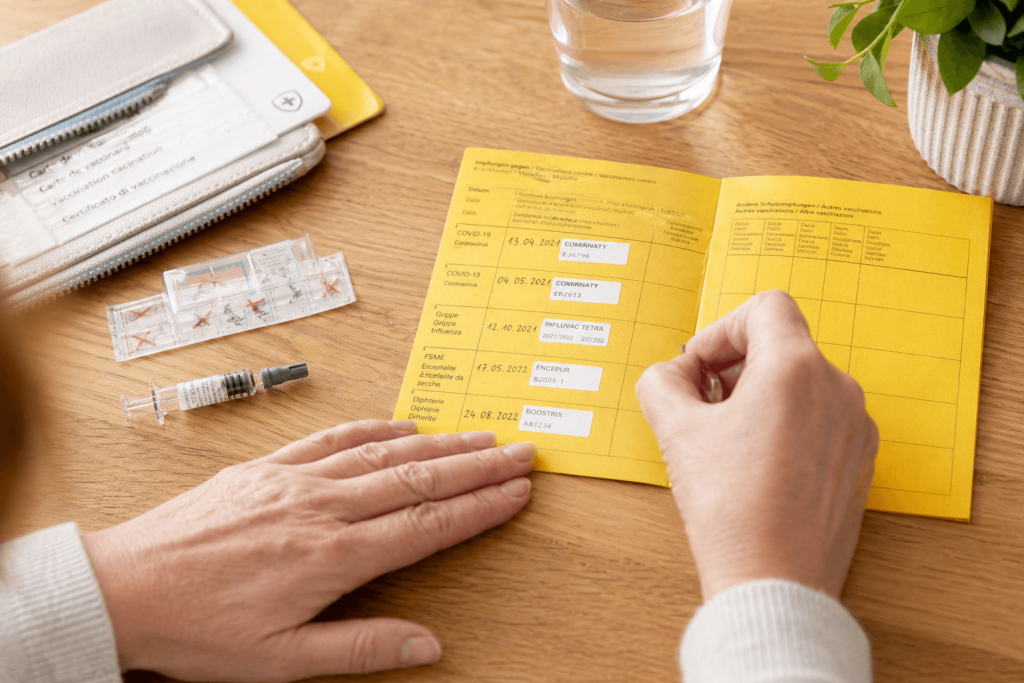

Booster: Oftmals nötig und empfehlenswert

Manchmal muss eine Impfung mehr als einmal verabreicht werden, damit genügend Antikörper gebildet werden, um im Ansteckungsfall eine genügend hohe Abwehr zu haben. Damit sich die Gedächtniszellen auch nach Jahren noch an den Erreger erinnern, ist bei einigen Impfungen nach einer gewissen Zeit eine Auffrischung (Booster) nötig.

Haben Sie Fragen zu Ihrem Impfstatus? Oder möchten Sie sich gegen die Grippe impfen lassen? Kommen Sie in Baden oder Dättwil vorbei – wir beraten Sie gerne.